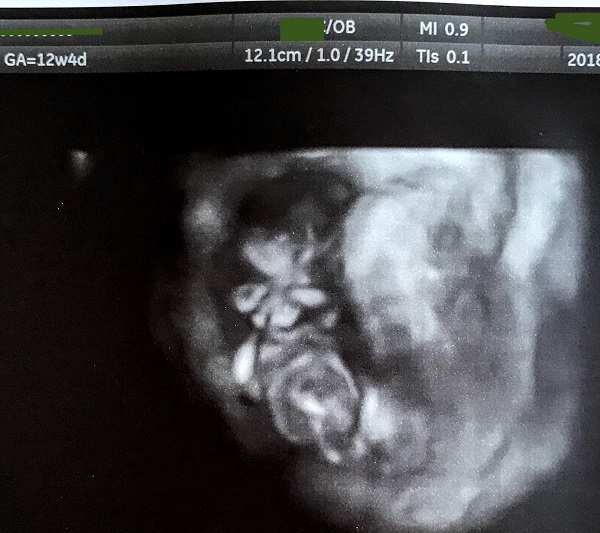

No, these are my only pics, unfortunately. I'm hoping that something can be discerned from the 3D shot, between the legs?

Sorry, no nub. Boy and girls look the same between the legs at this stage.

Hi,

Im not sure if I am seeing your 3D image correctly and you outline the area that the tech told you was between the legs?